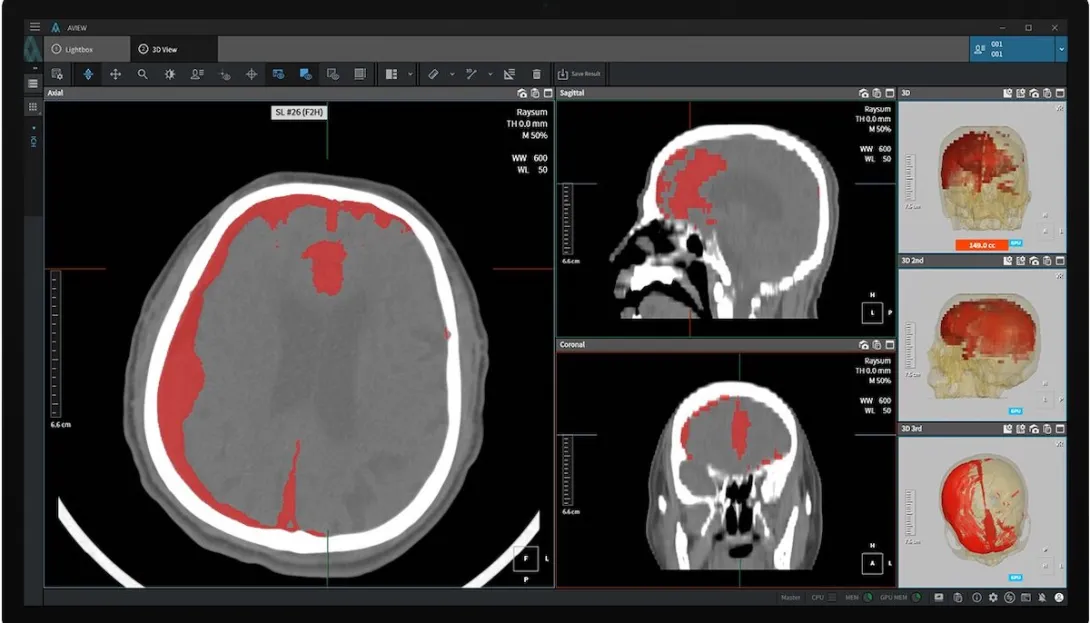

The software product called AVIEW Neuro CAD automatically detects cerebral haemorrhages in brain CT scans and sorts them according to severity. It was recognised as an innovative medical device in South Korea last year.